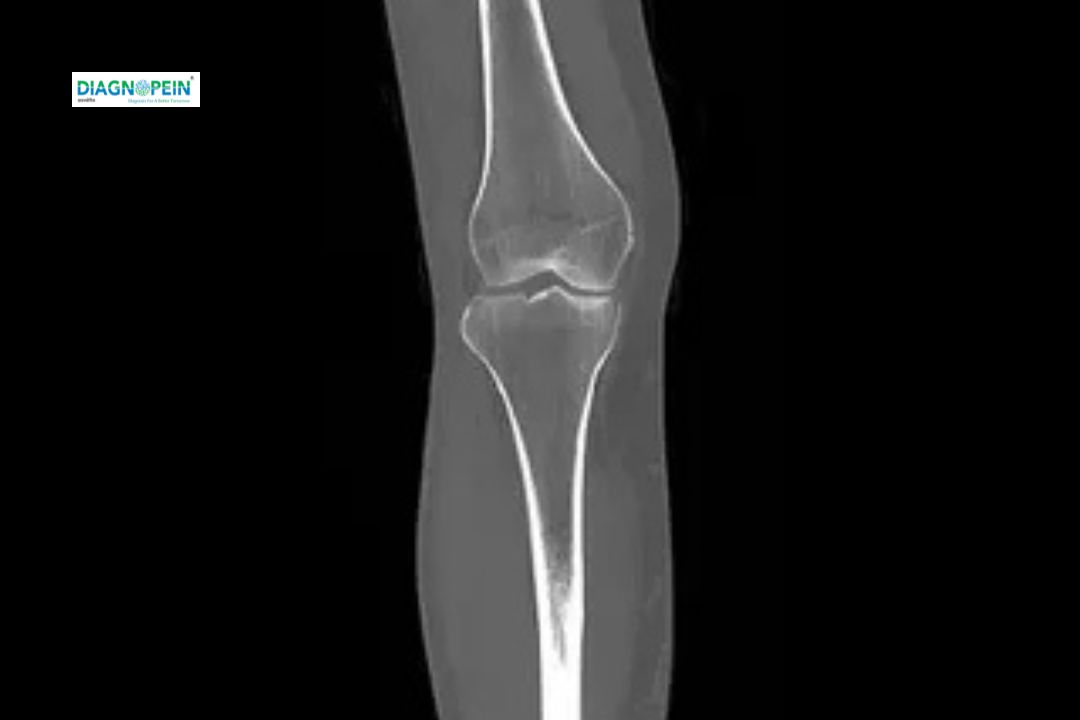

CT Right Knee Joint scan is an advanced diagnostic imaging test that produces detailed cross-sectional images of the knee using computed tomography technology. It provides a clear view of bones, ligaments, soft tissues, and the joint structure, making it an essential tool for detecting injuries or abnormalities that may not appear on a standard X-ray.

This scan is commonly recommended for patients with persistent knee pain, injuries from accidents or sports, or suspected bone fractures and infections. It is also valuable for assessing post-operative recovery and planning orthopedic surgeries.